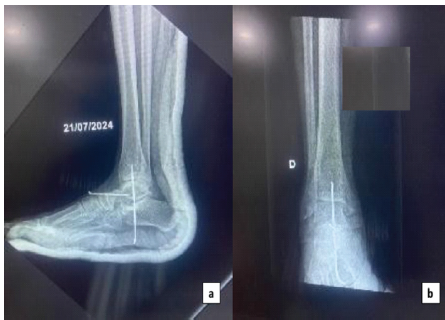

The reduction was stabilized with transarticular Kirschner wires across the talocalcaneal and talonavicular joints (Fig. 4).

Figure 4: Post-operative radiographs. (a) Lateral views of ankle showed perfect reduction stabilized with k-wire and (b) Anteroposterior view of the right ankle.